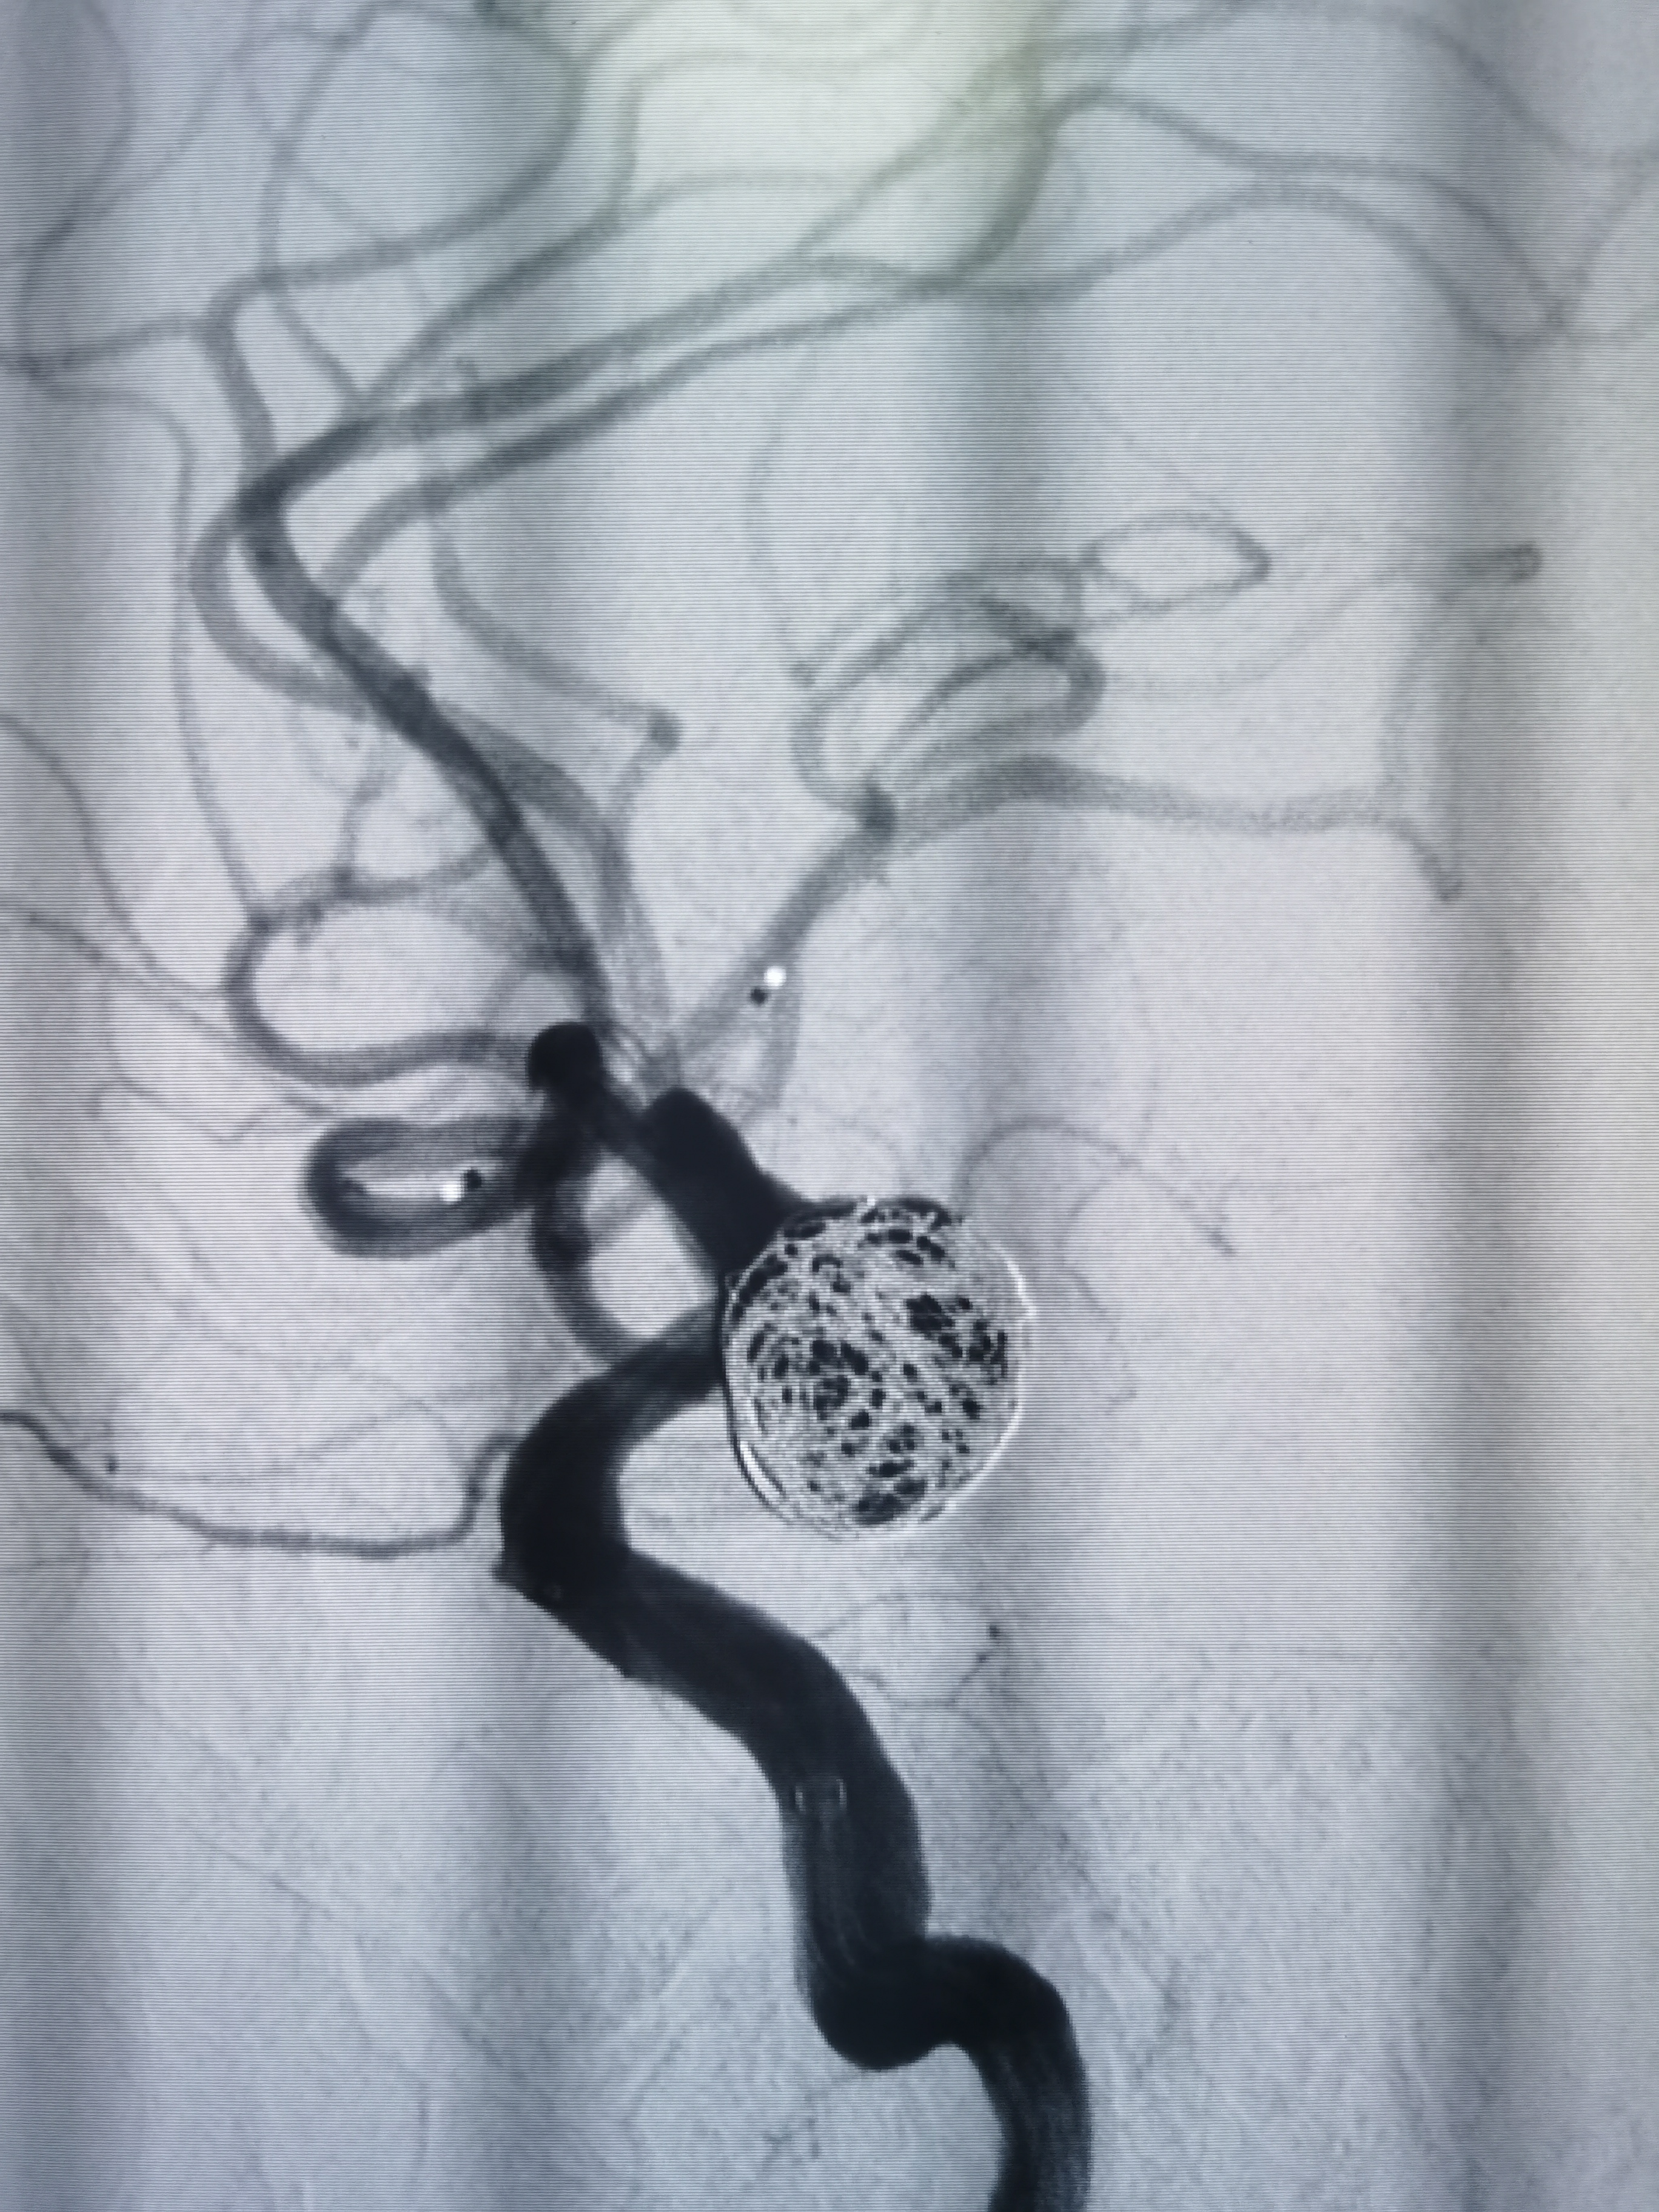

术后即刻造影见动脉瘤栓塞较完全。

术后造影见动脉瘤栓塞较为完全,载瘤动脉通畅,遂未再植入支架,逐渐撤出各级导管,缝合股动脉结束手术。